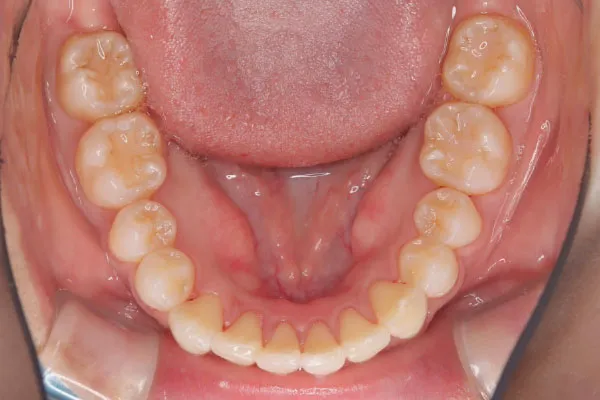

【20代女性】

ガタつきと斜めった歯を

インビザライン矯正で

治療したケース

治療前

| 主訴 | ガタつき、歯が斜め |

|---|---|

| 期間 | 2年 |

| 費用 | 220,000円〜660,000円 |

| 治療内容 | インザライン矯正 非抜歯 |

| 治療に伴うリスク | ・矯正終了後は、リテーナーを指示通りに使用し、歯の後戻りを防ぐ必要があります。 |